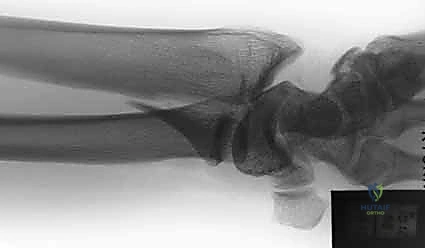

- الأشعة السينية (X-rays):

هي الخطوة الأولى لتقييم الكسر. يتم أخذ صور من زوايا متعددة (أمامية خلفية، جانبية، ومائلة) لتحديد موقع الكسر الأساسي ودرجة الانزياح والتقصير في عظم الكعبرة.

- التصوير المقطعي المحوسب (CT Scan) مع إعادة البناء ثلاثي الأبعاد:

هذا هو المعيار الذهبي الذي يعتمده الدكتور هطيف لجميع كسور المفصل المعقدة. تتيح الأشعة المقطعية رؤية كل شظية عظمية بوضوح تام، وتحديد حجمها، وموقعها، ودرجة تفتت السطح المفصلي بدقة ملليمترية. من خلال إعادة البناء ثلاثي الأبعاد (3D Reconstruction)، يمكن للدكتور هطيف "رؤية" الكسر من جميع الزوايا قبل فتح الجلد، مما يسمح له باختيار الغرسات (الصفائح والمسامير) الدقيقة لكل شظية وتحديد المداخل الجراحية المثلى.